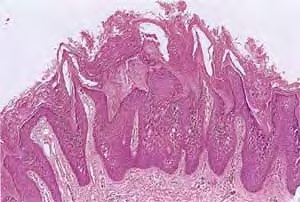

Histopathology. A characteristic histologic picture is seen in the epidermis and is referred to either as epidermolytic hyperkeratosis or as granular degeneration . It is present in bullous as well as in non bullous areas. There are variously sized clear spaces around the nuclei in the upper stratum spinosum and in the stratum granulosum. Peripheral to the clear spaces, the cells show indistinct boundaries formed by lightly staining material or by keratohyaline granules. A markedly thickened granular layer containing an increased number of irregularly shaped keratohyaline granules and compact hyperkeratosis is observed (14). When bullae form, they arise intraepidermally through separation of edematous cells from one another . The upper dermis shows a moderately severe, chronic inflammatory infiltrate. Mitotic figures are five times more numerous than in normal epidermis . Pathogenesis. Defects in keratin genes (KRT1 and KRT10) (16) are now known to be associated with this disorder. Mutations have been found in the carboxy terminal of the rod domain of keratin 1 and the aminoterminal of the rod domain of keratin 10 (17). The essential electron microscopic features are excessive production of tonofilaments and excessive and premature formation of keratohyaline granules; thus, at the periphery of the cells, numerous keratohyaline granules are embedded in thick shells of irregularly clumped tonofilaments (. The desmosomes appear normal, but the association of tonofilaments and desmosomes is disturbed, so many desmosomes are attached to only one keratinocyte instead of connecting two neighboring keratinocytes. Because of this disturbance in desmosomal attachment, blister formation takes place and real acantholysis occurs . Labeling with tritiated thymidine reveals greatly increased proliferative activity in the epidermis . It can be concluded that keratinization is both excessive and abnormal. Differential Diagnosis. Although the histologic picture of epidermolytic hyperkeratosis is diagnostic for the type of ichthyosis called epidermolytic hyperkeratosis, it is not specific for it. Hyperkeratosis is found also in several other seemingly unrelated conditions : epidermolytic keratosis palmaris et plantaris, solitary epidermolytic acanthoma, disseminated epidermolytic acanthoma, and linear epidermal nevus, usually of the systematized type. This latter entity was thought to be an entirely different condition than epidermolytic hyperkeratosis but with similar histologic findings. However, it is now known that epidermal nevi of the epidermolytic hyperkeratotic type are a mosaic genetic disorder of suprabasal keratin (l.e., point mutations of 10k alleles of epidermal cells in keratinocytes from lesional skin) that can be transmitted to offspring producing generalized epidermolytic hyperkeratosis . Epidermolytic hyperkeratosis can be an incidental finding in a variety of conditions